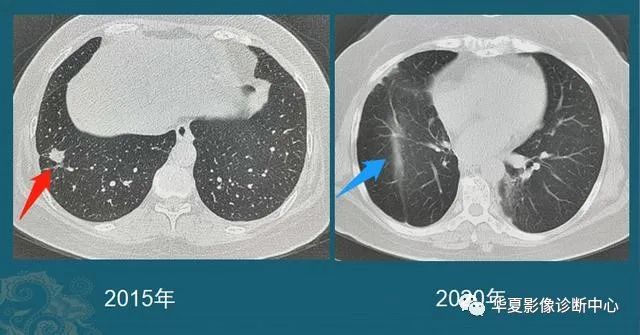

如何认识和理解肺腺癌外科治愈窗口期

如何认识和理解肺腺癌外科治愈窗口期